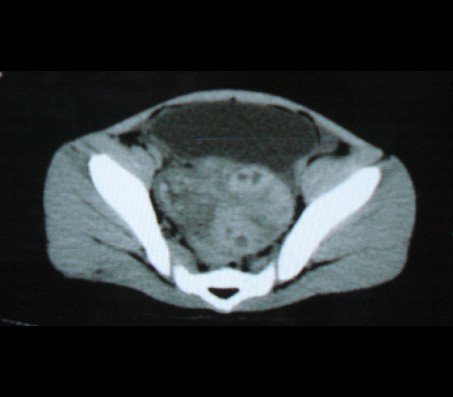

标题: PED0942:女性,8岁,B超提示盆腔病变,请会诊! [打印本页]

标题: PED0942:女性,8岁,B超提示盆腔病变,请会诊!

畸胎瘤

考虑畸胎瘤可能性大!